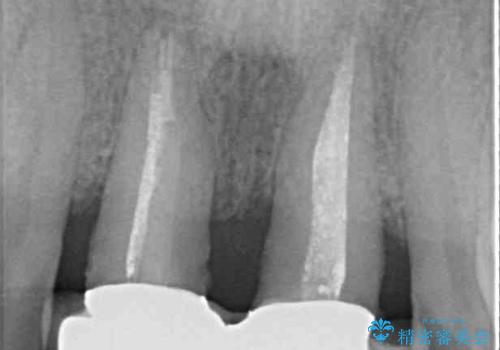

不適合なクラウンが装着されていたため、歯周ポケットが深くなっていましたので、矯正治療前に歯周外科処置を行って歯周ポケットを除去し、矯正治療後にオールセラミッククラウンにて補綴治療を行うこととしました。

- 隙間の空いた前歯をセラミッククラウンで補隙したところ、歯肉から出血してしまい、何とかしたいとのことで来院された患者様です。